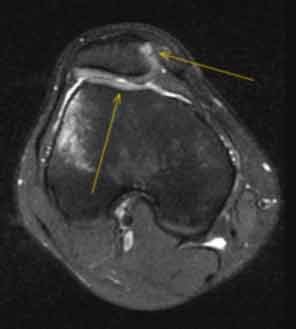

MRI-Bildgebung nach Kniescheibenluxation/Auskugelung, die gelben Pfeile markieren das Knochenmarködem sowie die Zerreissung des MPFL (oberer, rechter Pfeil).